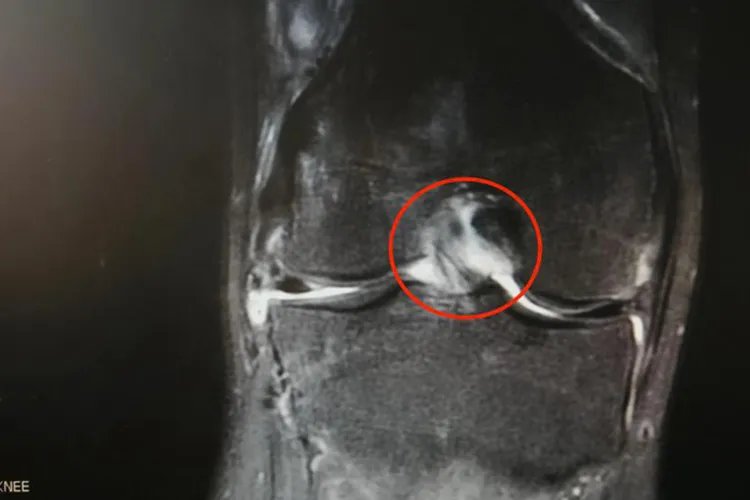

膝关节结核患者同样存在低热、乏力等全身症状。膝关节结核患者的膝关节位置表浅,因此肿胀和积液十分明显。膝眼饱满,髌上囊肿大,浮髌试验阳性。较晚期,滑膜可以显著肿胀和增厚。早期膝关节穿刺可获得比较清凉的液体,随病程发展,抽出液体逐渐变浑,纤维素混杂在内,最终变为脓性。膝部呈梭形肿胀,日久发生屈曲挛缩。后期寒性脓肿形成,破溃后呈慢性窦道,经久不愈合,可出现病理性脱位等。